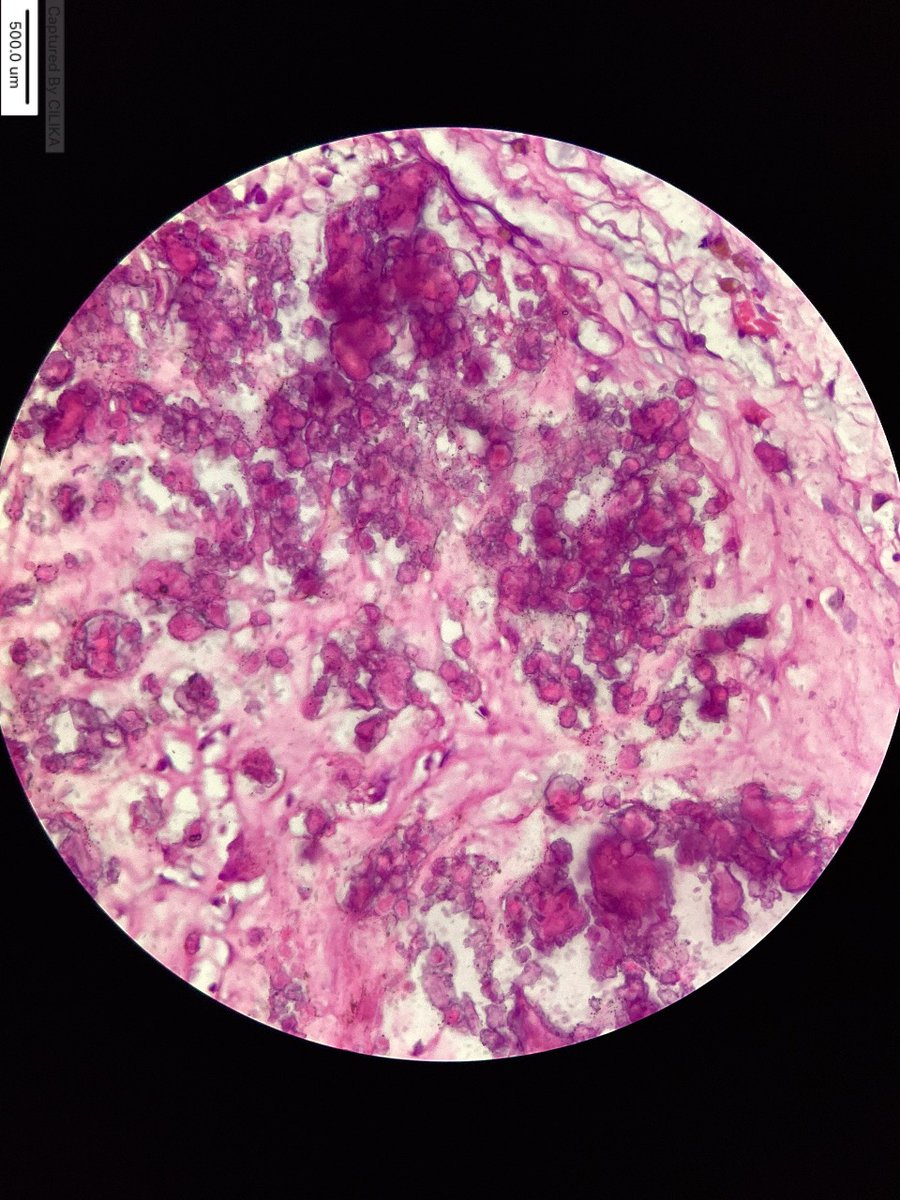

#MTPathUnknown #269

Another finding in decomposed body.

Two images--first is lower power, second is higher power (and maybe a little easier).

Hint: common finding at autopsy

What is the most likely diagnosis?